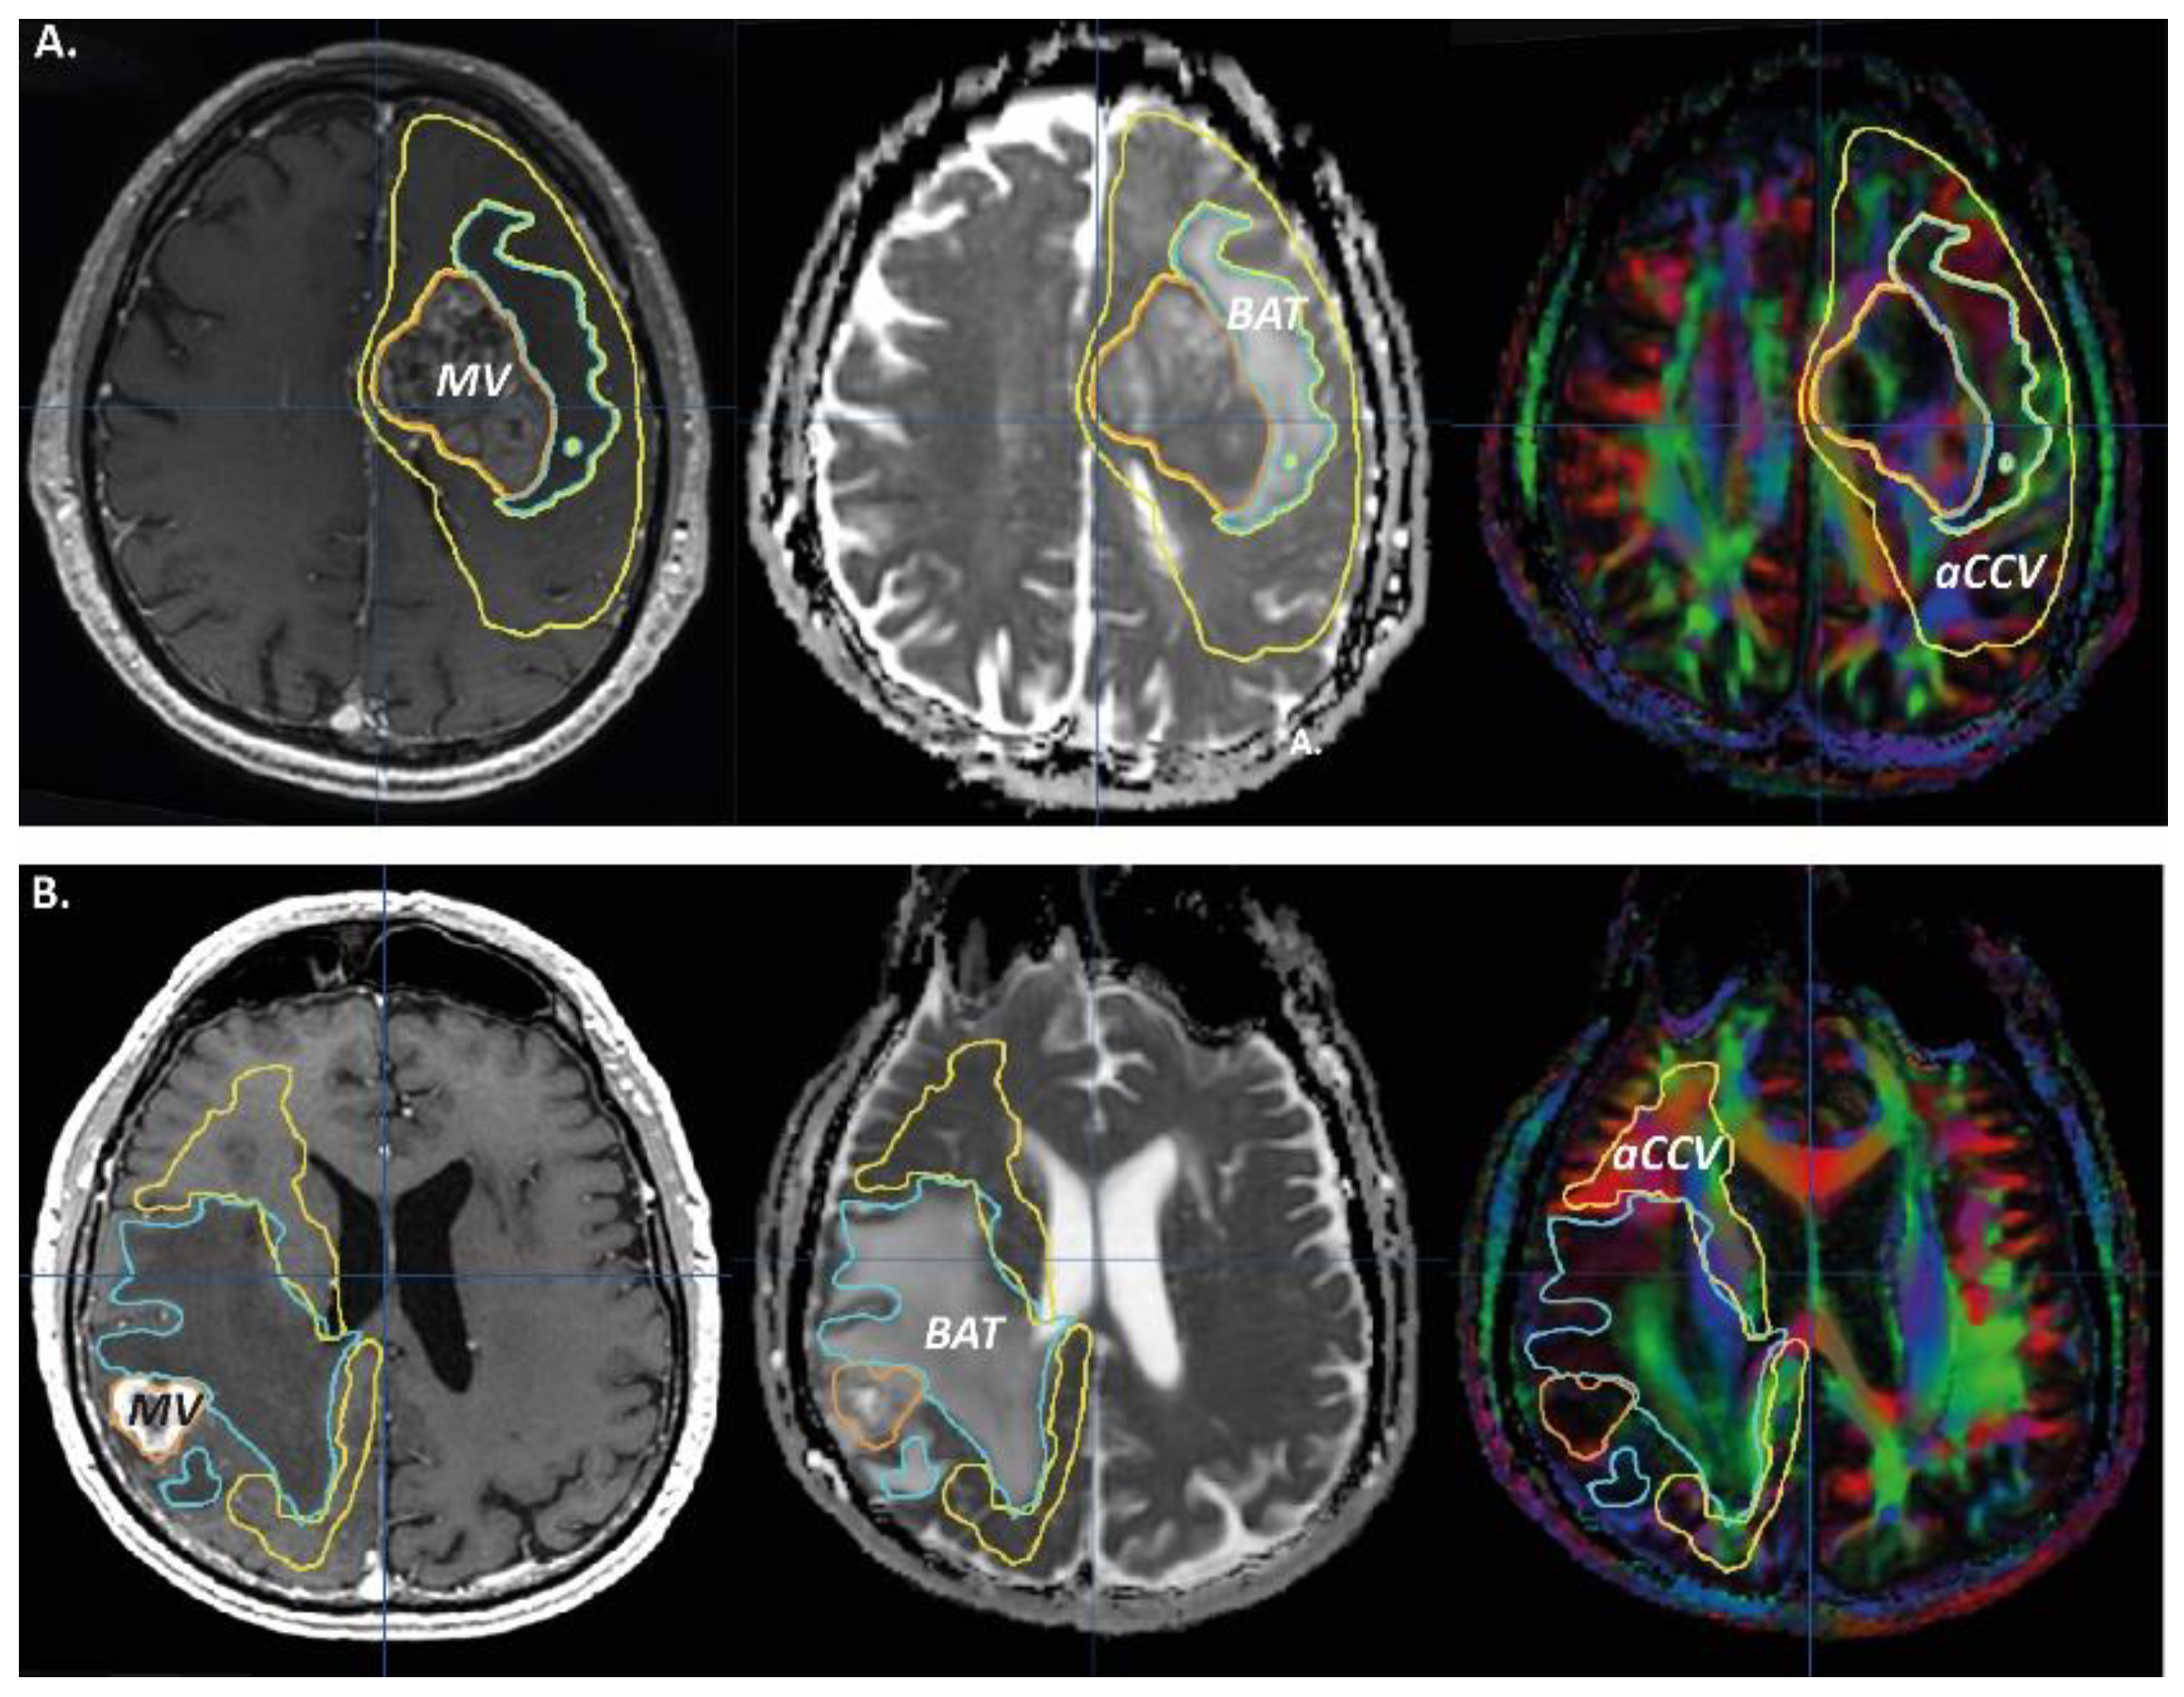

2.3. MRI Objects